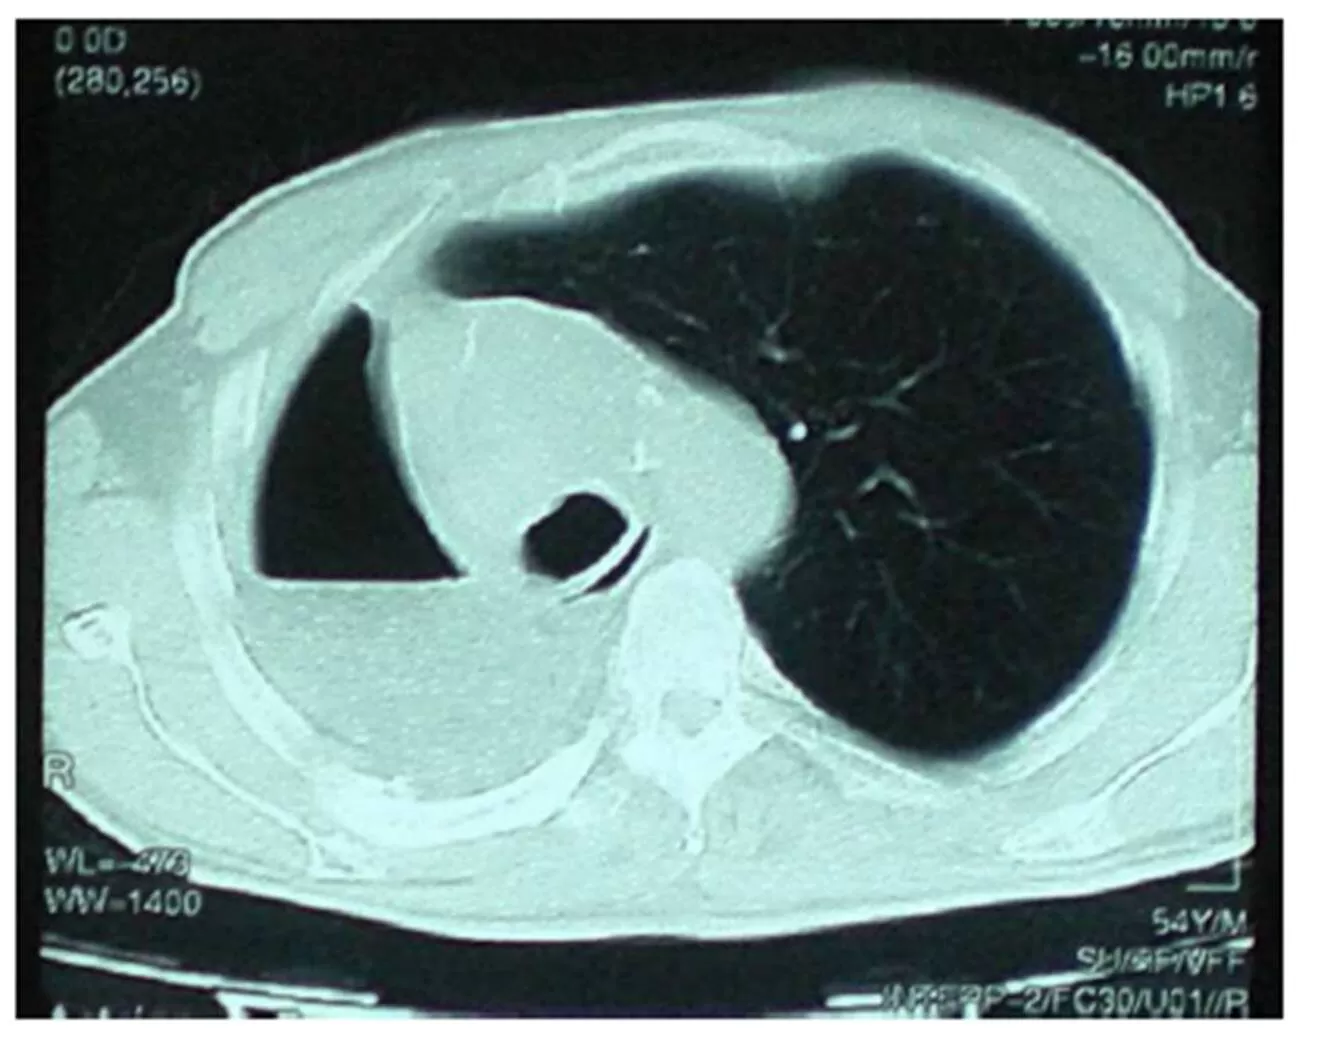

Three months later, the patient stated that he was coughing up foul smelling sputum. Another bronchoscopic biopsy was conducted and ‘squamous metaplasia and histiocytic giant cells with foreign bodies (suspected suture material) within their cytoplasms’ were reported by our colleagues in pathology department.  There was a 19 mm density with air loculations at the right anterior lateral side of his distal trachea in thorax CT (Fig. 1).

Postoperative control Thorax CT

Figure1: Postoperative control Thorax CT